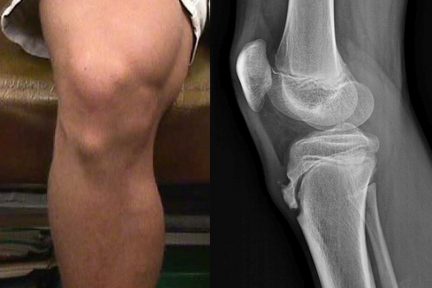

Дано определение болезни Осгуда-Шлаттера, Описаны факторы риска возникновения болезни: возраст, пол, занятия спортом, низкий уровень витамина D,  избыточная масса тела подростка. Приведены рекомендации по профилактике и лечению болезни…